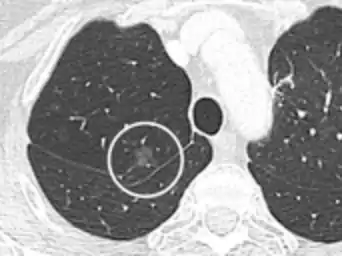

- A lung nodule abutting a pulmonary cyst is a rare finding, yet indicating cancer.[9]

- Bubble-like lucencies in the nodule indicate cancer:[9]